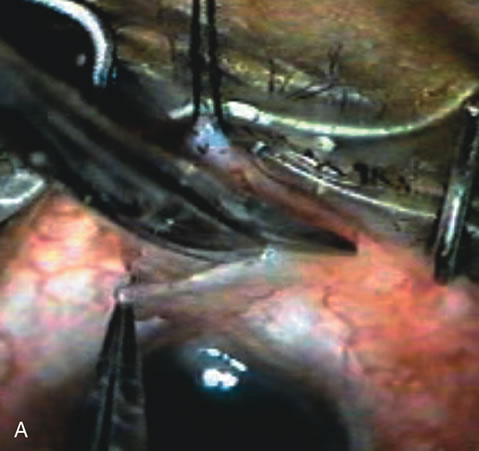

CASE 6: ANTICIPATED LENS EXTRACTION POST FAILED TRABECULECTOMY WITH ADVANCED DISC DAMAGE AND IOP OUTSIDE TARGET PRESSURE RANGE

The inflammation associated with lens extraction at any site usually causes complete failure of a marginal functioning bleb. In addition, pressure reduction by medical means is usually minimal in these recalcitrant cases, and combined surgery is indicated. In the past, these cases were approached with large-incision ECCE, clear corneal cataract incision, and bleb revision. Drawbacks included those mentioned earlier for large incision clear corneal cataract extraction, and bleb revision is often associated with conjunctival buttonholes, wound leaks, subconjunctival hematoma, destruction of friable sclera, and associated hypotony. With the advent of modern-day cataract surgery, a phacotrabeculectomy is often possible adjacent to the failed filter (Fig. 7). The ability to combine cataract extraction with implant and filtration surgery all through the same small incision has greatly improved outcomes for patients with marginal preoperative filters. There are several other viable options in this case. If the surgeon elects to remove the cataract through a temporal clear corneal incision, the bleb may be revised or a new adjacent filter fashioned. As mentioned earlier, revising a failed filter is technically challenging. If the surgeon believes it is not feasible to revise the filter or fashion a new one, a glaucoma drainage implant is a reasonable option combined with temporal lens extraction.172

Fig. 7. Phacotrabeculectomy adjacent to a failed filter in cataractous eye. The ability to combine small-incision cataract extraction with trabeculectomy all through the same incision adjacent to the failed filter allows the surgeon to work in a familiar superior area. Avoiding incisions into the existing bleb decreases conjunctival buttonholes, hypotony, operating room time, and subconjunctival bleeding. A. Appearance of failed bleb with exposure of superior temporal quadrant gained with a corneal traction suture. B. Prepare a limbus-based conjunctival flap and a scleral flap. C. This bleb is at high risk to fail again justifying the need for MMC, 0.2 mg/cc applied on a pledget for 4 minutes. D. Insert the keratome and perform phacotrabeculectomy in the usual fashion.